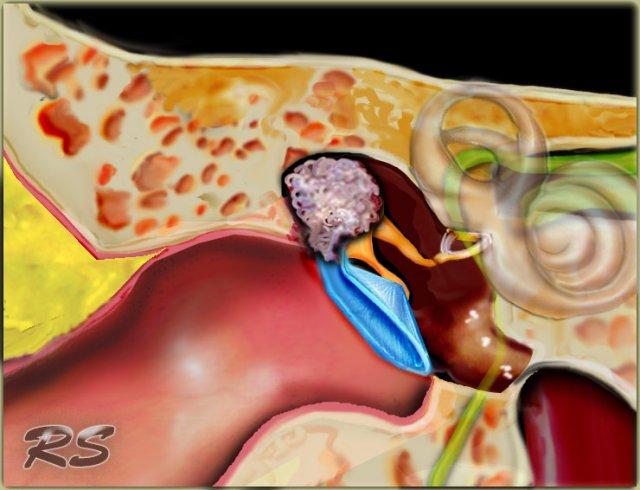

Bên trái là hình minh họa u cholesteatoma.

Tổn thương này sẽ được thảo luận ở phần sau.